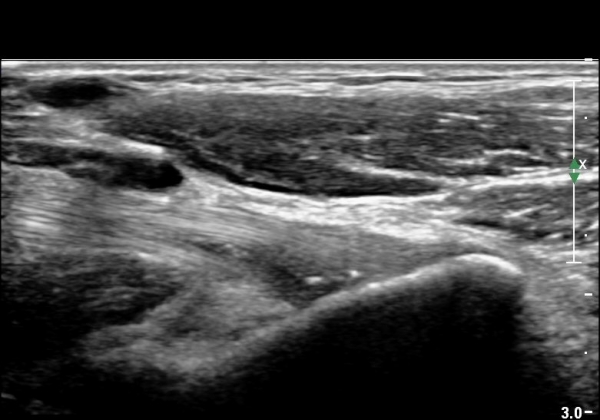

ŽÃËÀÚ¸¦ Á¶±Ý ¸»´ÜÀ¸·Î À̵¿Çϰí ŽÃËÀÚ¸¦ ¸Ó¸®ÂÊÀ¸·Î ±â¿ïÀÌ´Ï À̵ιڱٰÇÀÌ ¶Ñ·ÈÇÏ°Ô °üÂûµÇ´Âµ¥ À̵ιڱٰÇÀÇ ºÎÁ¾ÀÌ °üÂûµÊ(±×¸² 3).

Á¶±Ý ´õ ¸»´ÜÀ¸·Î À̵¿ÇÏ¿© °üÂûÇÏ´Ï ÀÌµÎ¹Ú±Ù°Ç ½ÇÁú³» ÆÄ¿­°ú °üÀý ÁÖÀ§ ¼ö¾×Àú·ù°¡ °üÂûµÊ(±×¸² 4, 5).